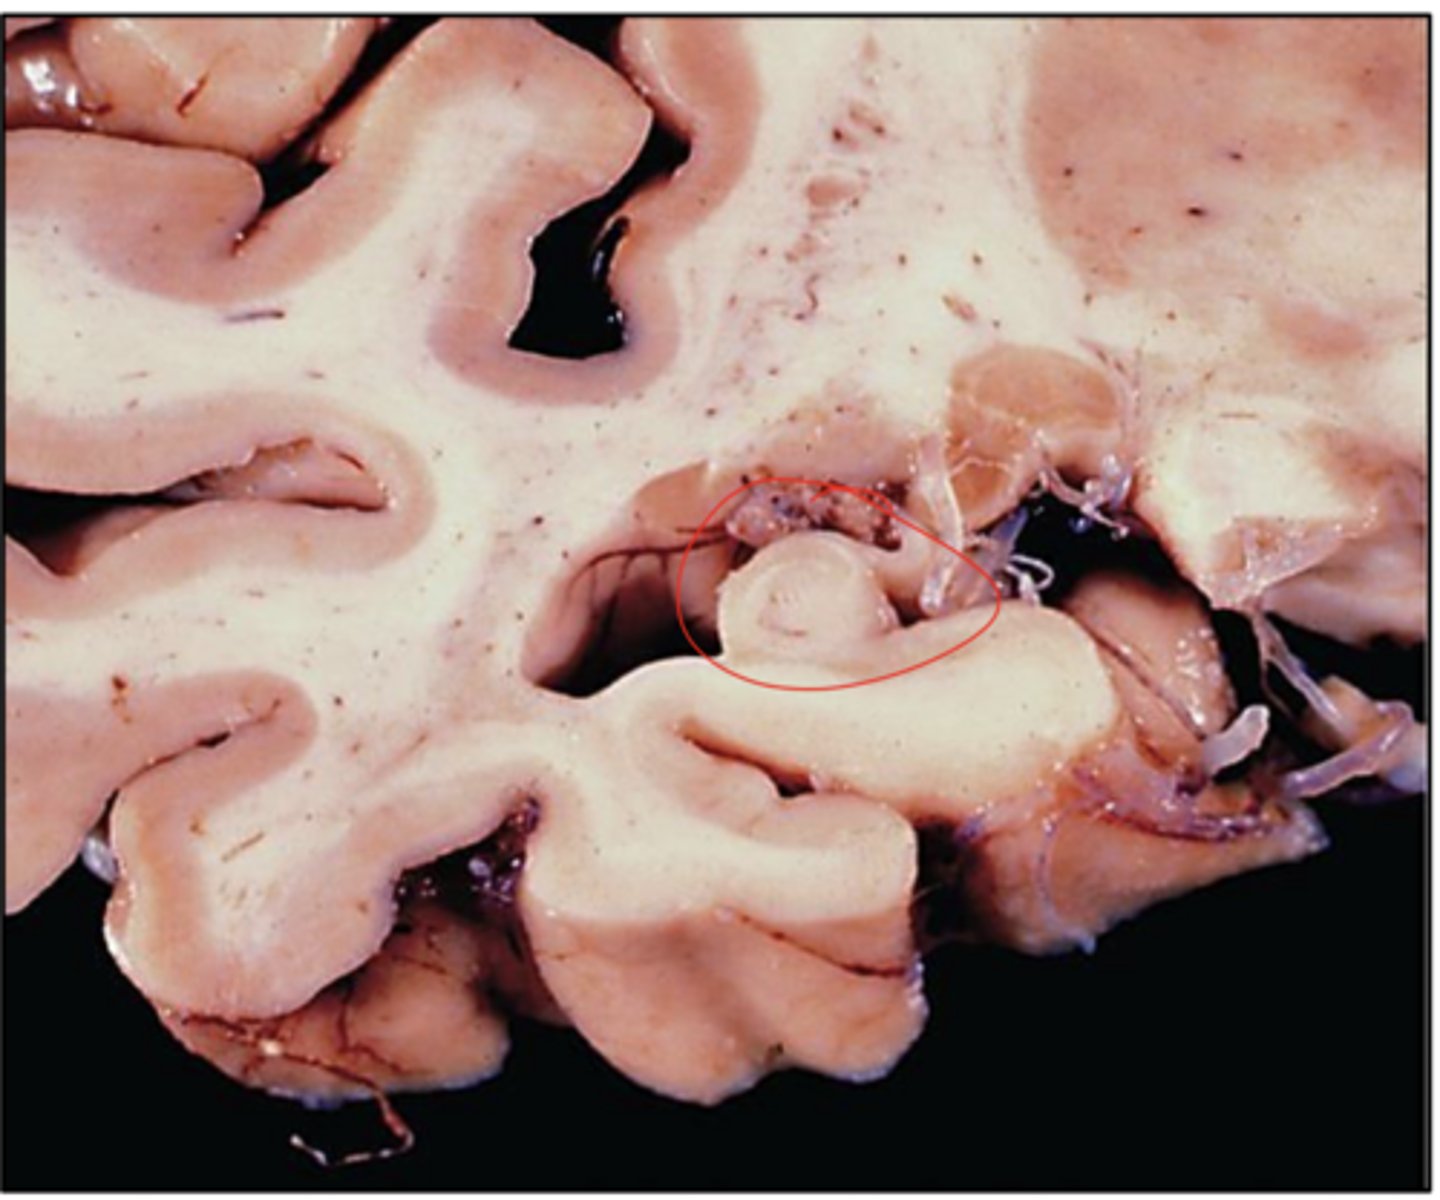

in the parieto-occipital region

Where is cerebral amyloid angiopathy (CAA) more prominent?

note the hyalinized, thickened vessel wall on the left